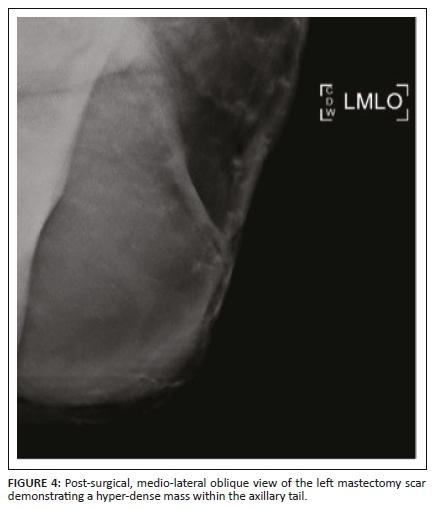

The patient then defaulted on her follow-up appointments including an appointment for a staging CT scan. Five months after the mastectomy, she was referred for a repeat mammogram and ultrasound for multiple large lesions at the left mastectomy site. The mammogram of the left scar demonstrated a 50 mm × 60 mm hyper-dense mass within the axillary tail as displayed in Figure 4. Ultrasound of the left mastectomy site demonstrated round hypoechoic lesions at the scar as demonstrated in Figures 5a and 5b. The largest measured 20 mm × 11 mm, situated at the inferior-lateral aspect of the scar and not separable from the underlying pectoralis muscle. Large axillary masses consisting of fluid with areas in keeping with soft tissue densities were demonstrated; the largest measured 56 mm × 38 mm. The lesion was classified as BI-RADS 4C. Ultrasound-guided core biopsy of the largest lesion demonstrated a poorly differentiated malignancy with OGCs - features in keeping with recurrence. The patient underwent a single cycle of radiotherapy and was then referred to oncology where she was treated with adriamycin and continues follow-up.